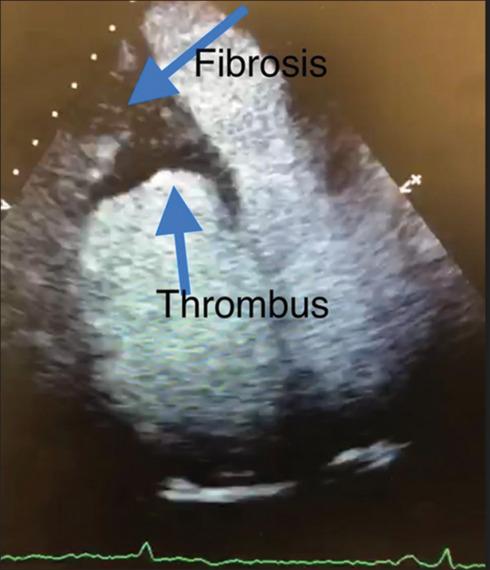

Loeffler first described "fibroplastic parietal endocarditis with blood eosinophilia" in 1936. This we now know refers to the most common cardiac manifestation of an uncommon condition, the so-called hypereosinophilic syndromes. This condition typically results in a restrictive cardiomyopathy affecting the left heart, but here, we present an unusual case of a 65-year-old woman with chronic hypereosinophilia of at least 2 years, who presented with right heart failure as a result of eosinophilic endomyocardial infiltration of her right ventricle. We explore the diagnostic pathway and look at the literature on management.

勒夫勒于1936年首次描述了“伴有血液嗜酸性粒细胞增多的纤维增生性心内膜炎”。我们现在知道,这指的是一种罕见病症(即所谓的嗜酸性粒细胞增多综合征)最常见的心脏表现。这种病症通常会导致影响左心的限制性心肌病,但在此,我们报告一例不寻常的病例,一名65岁女性,患有至少2年的慢性嗜酸性粒细胞增多症,因右心室嗜酸性粒细胞性心肌内膜浸润而出现右心衰竭。我们探讨了诊断途径并查阅了有关治疗的文献。